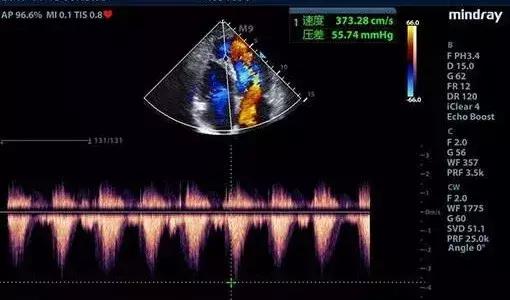

彩超具有彩色多普勒血流显像功能,可以显示病变区域的血管解剖结构、血流方向、血流速度和血流状态改变,可以明显提高对疾病的鉴别能力,提高诊断的准确性。

超声心动图检查系将超声探头置于胸壁、食管内,对立体的心脏进行无数切面扫描、综合分析心脏各结构的位置、形态、活动与血流特点,从而获得心血管疾病的解剖、生理、病理及血流动力学诊断资料。近年来食管内超声进一步拓宽其应用范围,大大提高了诊断敏感性与特异性。

2、心瓣膜病变:对心瓣膜狭窄、关闭不全、瓣叶钙化、脱垂、穿孔、瓣环钙化、赘生物附着、瓣叶发育畸形等病变均能作出明确诊断。